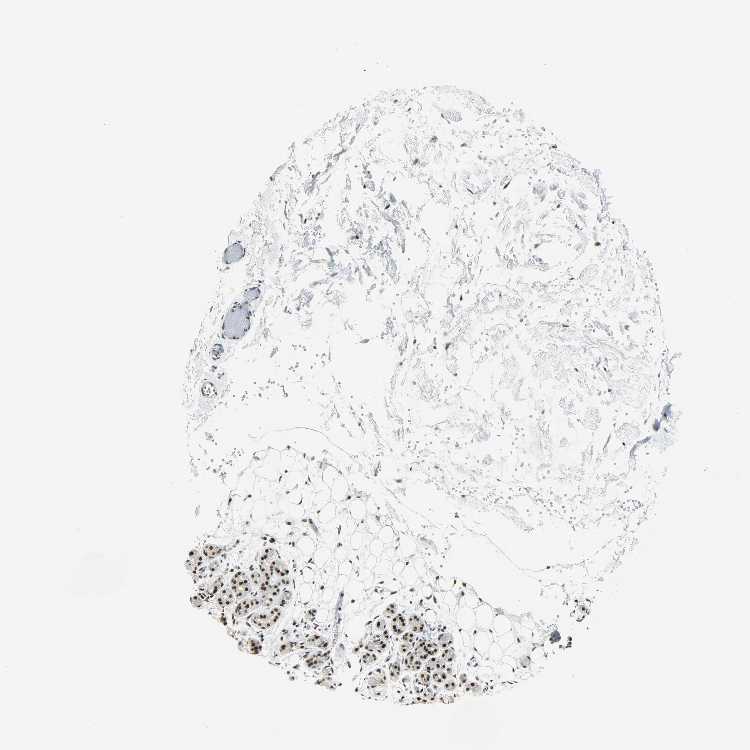

Antibody HPA004890

Glandular cells High